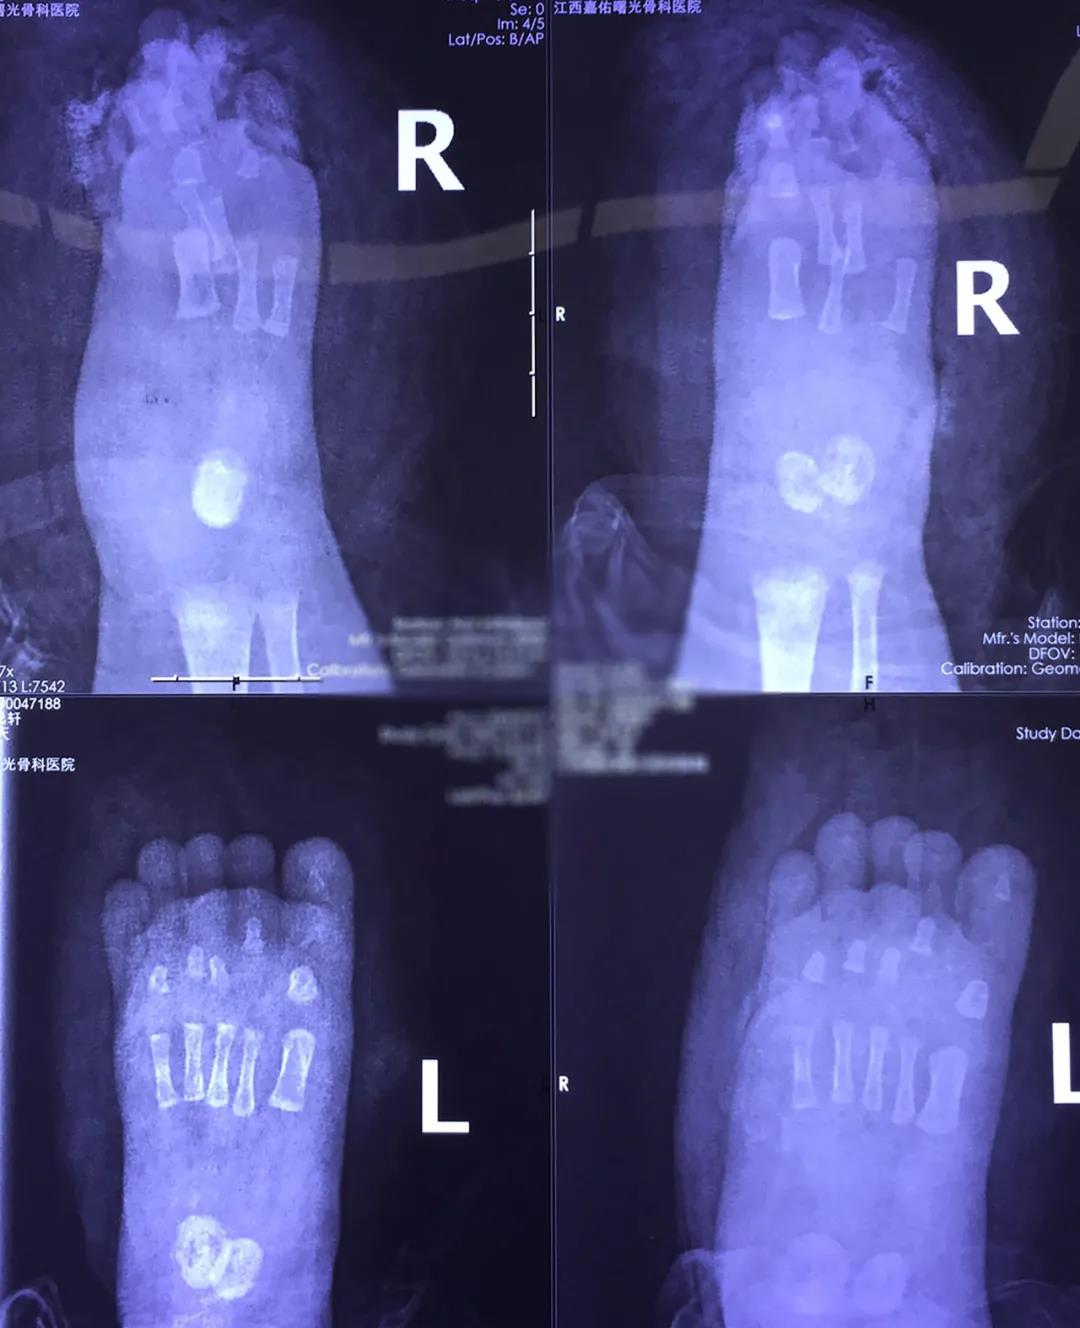

“双足碾压伤,并右足多趾毁损、头部外伤、全身多处外伤。”急诊医师时间给出初步诊断后,急诊科护理团队配合值班医生快速建立静脉通道,抢救轩轩生命。

足部毁损伤严重,保肢条件不乐观。为最大限度保住轩轩脚掌及功能,多学科联合会诊后,由邓名山主任携周伟医生等手足外科团队,勇闯低龄手术险区,为小轩轩进行手术。

术中出血仅20ml,手术顺利完成。术后,轩轩被安排在ICU病房,24小时密切监护生命指征,并予以对症治疗。

一眨眼,两个月的时光过去了。前前后后,轩轩共经历了5次手术。一次次清除坏死组织、残端修整、植皮手术……轩轩的脚掌顺利保住,在家人和医护团队的护送下出院。